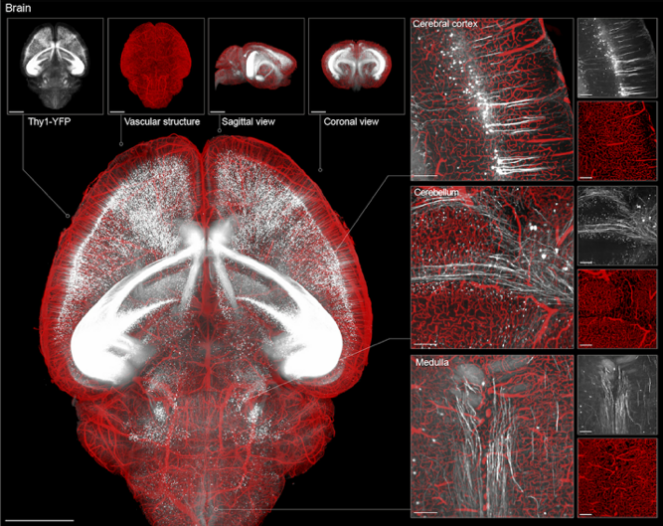

VIVIT重构脑组织三维全景